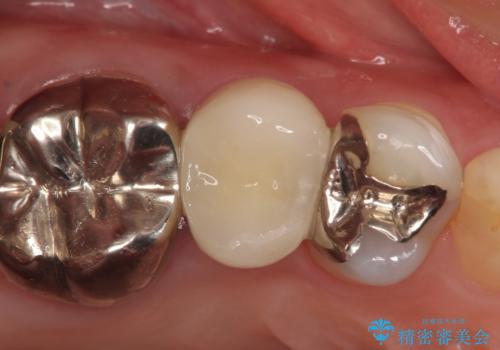

診査の結果神経を保存するのは困難だったため、根管治療を行った後、オールセラミッククラウンによる補綴を行いました。

今回用いたオールセラミッククラウンはジルコニアフレームという白い素材の上にセラミックを盛っているため、審美性が非常に高いのが特徴です。

また、ジルコニアは人工ダイヤモンドの材料にも使われているほど高い強度を持っており、そのためオールセラミッククラウンは審美性だけでなく、奥歯やブリッジの補綴も可能とするクラウンです。